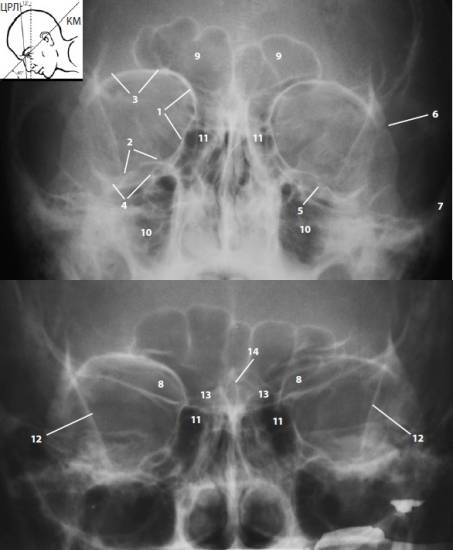

в — передняя полуаксиальная (подбородочная) проекция Waters,

- передняя полуаксиальная (подбородочная) проекция Waters. Лежащий на животе пациент касается кассеты лишь подбородком, кончик носа располагается в 0,5-1,5 см над кассетой. Угол между кантомеатальной линией и центральным рентгеновским лучом составляет 37-45°.

Благодаря отчетливому изображению верхней глазничной стенки, а также передней и средней третей нижней глазничной стенки проекция полезна для визуализации смещенных по вертикали фрагментов крыши и дна, в том числе диагностики их «взрывных» и вдавленных переломов.

При интерпретации снимка следует помнить, что из-за особенностей укладки изображение дна глазницы оказывается на 10 мм ниже контура подглазничного края. Таким образом, полноценный анализ состояния нижней стенки глазницы предполагает использование подбородочной и носолобной укладок.